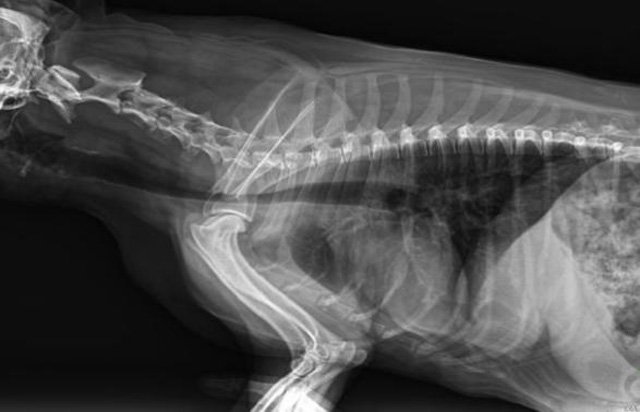

从临床角度出发,大力发展动态DR,以精准的诊断为小动物保驾护航。宠物DR升级使用双焦点球管,大尺寸平板探测器,超高频逆变高压发生器。医用纤维板台面,防止宠物划伤。宠物DR整机小巧实用,骨略结构和器官位置,分类详细,运算更快,让拍摄条件更科学,有助于提高诊断的准确性和效率。安装移动非常方便。低输入电流设计,220伏常规电压。多品种动物程序设定,满足各个临床需求。成像效果显著,宠物不能言语表达,导致误诊率居高不下。宠物诊疗均以经验诊断为主的方式,确保最小化辐射降低对医生及动物的影响。以满足精细化的宠物医疗需求,成为诊断宠物内外科疾病的必备工具。使医院更有竞争力,为医院创收增光添彩。

宠物DR的操作流程是什么呢?第一步首先插上整机电源,然后按下主机电源。打开高压发生器的电源,工作站主机电源。等待主机软件的自动启动。通过软件登记检查的宠物信息,选择宠物检查拍摄部位。调节限速器拍摄区域。关闭铅房门,点击开始拍摄按钮。拍摄完成调整图像并且输出。